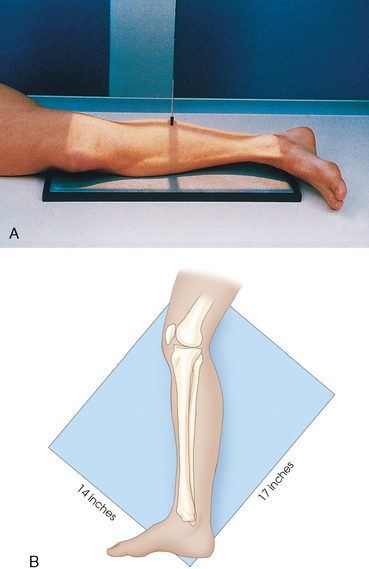

For this projection and the lateral and oblique projections described in the following sections, the long axis of the IR is placed parallel with the long axis of the leg and centered to the midshaft. Unless the leg is unusually long, the IR extends beyond the knee and ankle joints enough to prevent their being projected off the IR by the divergence of the x-ray beam. The IR must extend 1 to 1½ inches (2.5 to 3.8 cm) beyond the joints. When the leg is too long for these allowances, and the site of the lesion is unknown, two images should always be made. In these instances, the leg is imaged with the ankle joint, and a separate knee projection is performed. Diagonal use of a 14 × 17 inch (35 × 43 cm) IR is also an option if the leg is too long to fit lengthwise and if such use is permitted by the facility. The use of a 48-inch (122-cm) SID reduces the divergence of the x-ray beam, and more of the body part is included.